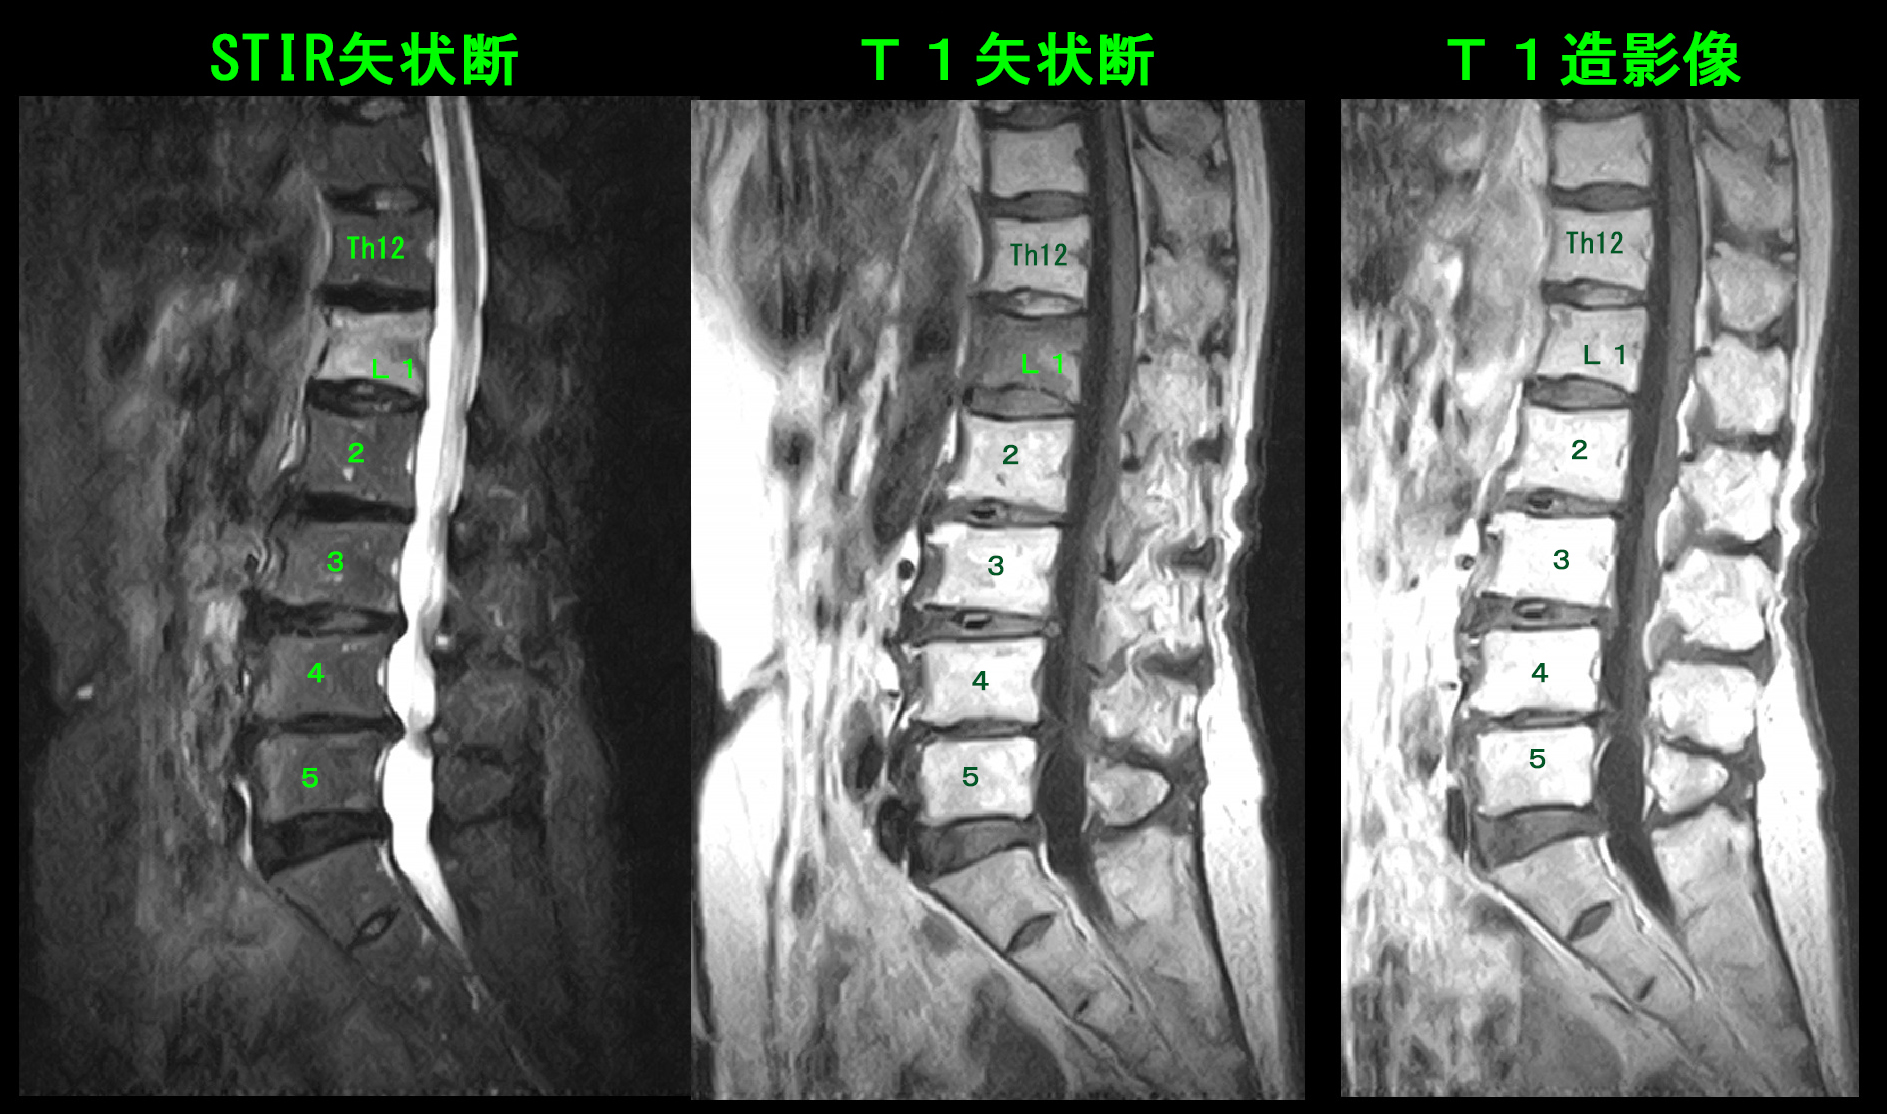

81才女MR1.jpg

MRI検査ではL1はSTIR条件では高輝度と(白く)なっており、T1条件では低輝度と(黒く)なっており、これは骨が壊れていることを示す所見です。T1の造影像ではT1の条件で黒かったL1が白く造影されており、これは安静が保て、しっかり治療されれば椎体の扁平化が防止できる所見です。骨粗鬆薬の処方を開始するとともに、VAS10の痛みは辛かろうと強めの痛み止めトアラセットを1日4回で(朝・昼・夕・寝る前)処方しました。